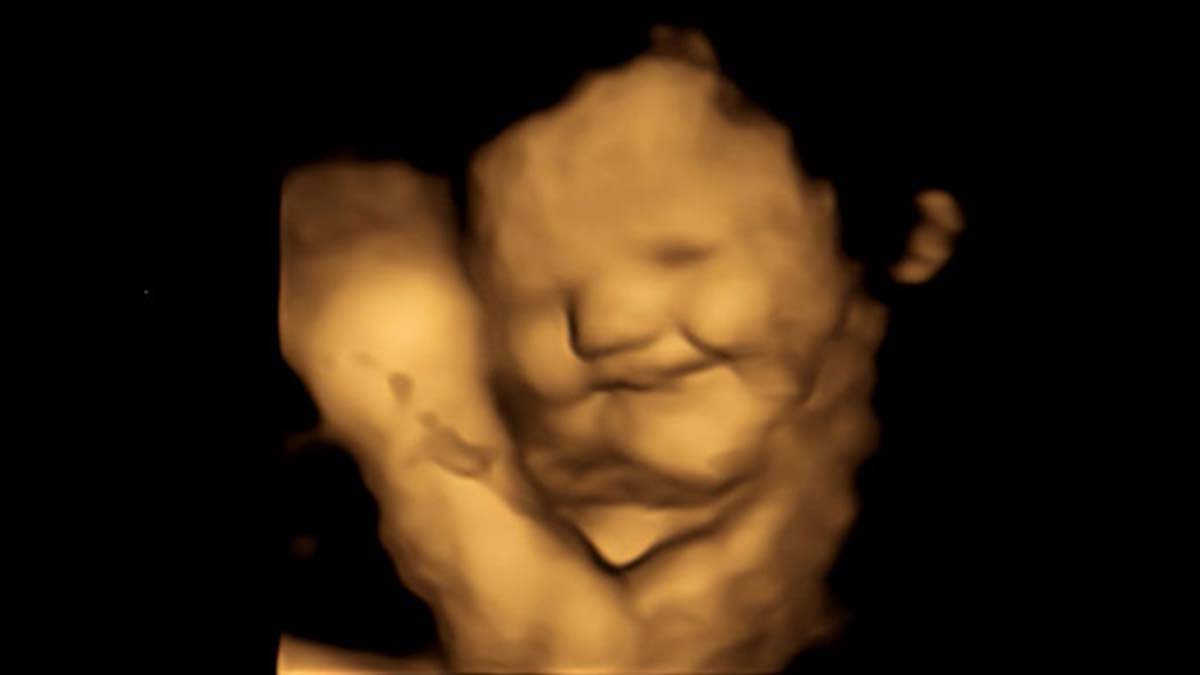

Un grupo de científicos captó la expresión facial de bebés dentro del útero ante la ingesta de ciertos alimentos por parte de la madre. Para ello, emplearon ecografías 4D con un resultado sorprendente.

En el caso de la zanahora, los fetos mostraron "cara de risa", aunque en el caso de la col obtuvieron "cara de llanto", dijo la casa de estudios.

"Fue realmente sorprendente ver la reacción de los bebés no nacidos a los sabores de la col rizada o la zanahoria durante las exploraciones y compartir esos momentos con sus padres", explicaron los investigadores.